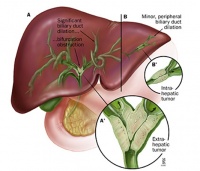

1.肝外胆管癌的发生部位在解剖学上根据癌发生的部位肝外胆管癌可分为:①左右肝管癌;②肝总管癌;③胆囊管癌;④肝总管胆囊管及胆总管汇合处癌;⑤胆总管癌

2.肝外胆管癌的大体形态:肝外胆管癌在大体形态上可分为三型:

①管壁浸润型:可见于胆管的任何部位最为多见由于受累的管壁增厚可致管腔变小或狭窄进而可发生阻塞现象

②结节型:较管壁浸润型少见可见于较晚期的胆管癌癌结节的直径可1.5~5.0cm

③腔内乳头状型:最少见可见于胆管的任何部位但汇合部更为少见此型可将胆管腔完全阻塞癌组织除主要向管腔内生长外亦可进一步向管壁内浸润生长